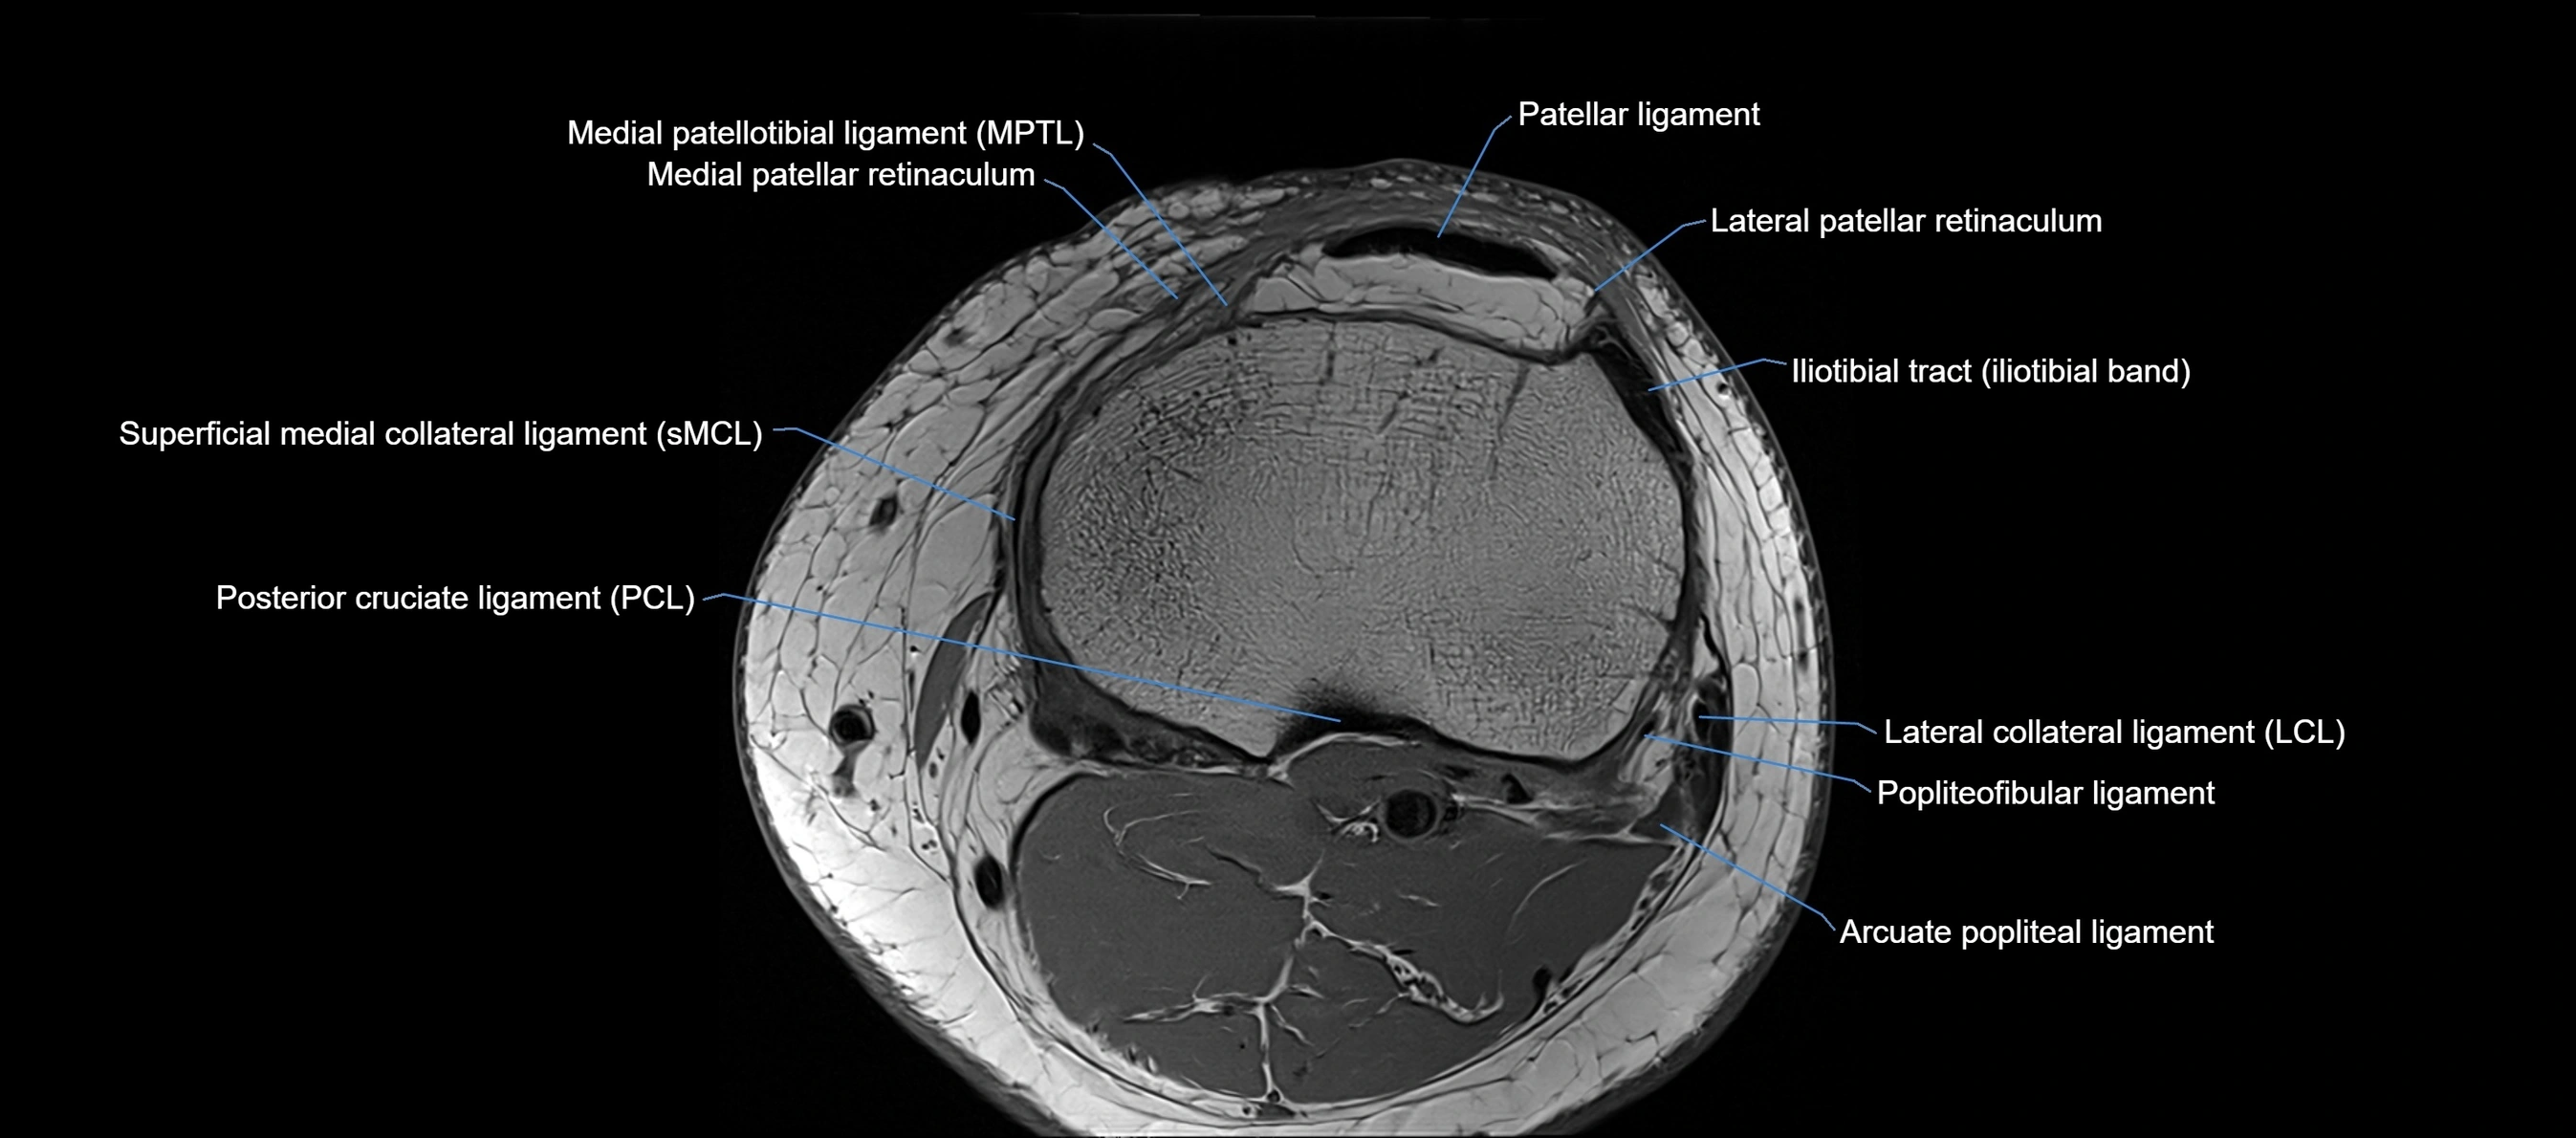

MRI images

image